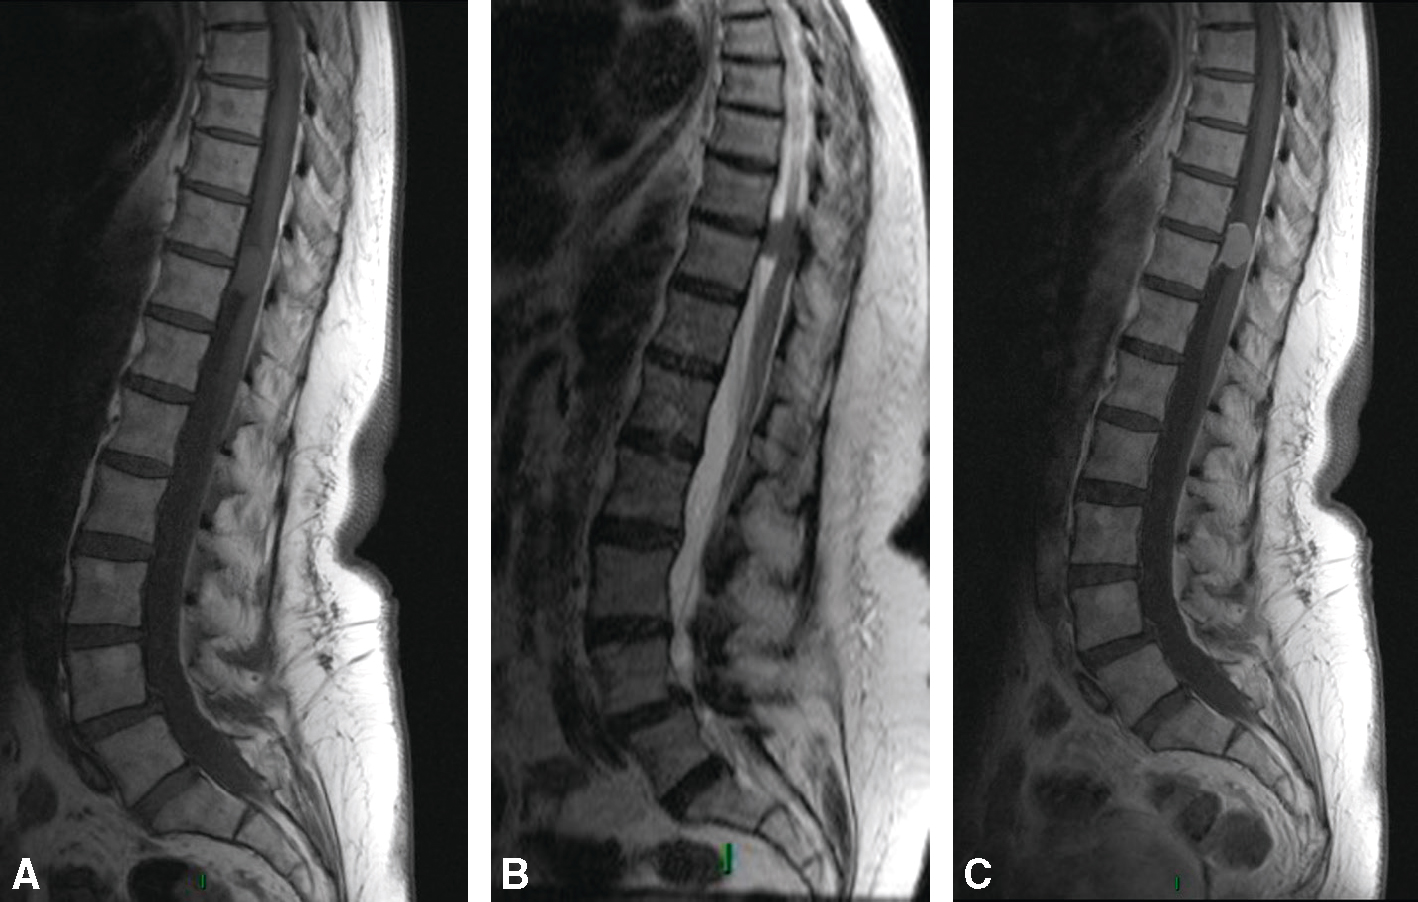

Volumineux processus expansif du cône terminal étendu de T8 à L1, en hyposignal T1 et T2, avec quelques prises de contraste nodulaires au sein de la lésion après injection. Pas de prise de contraste radiculaire; intégrité des corps vertébraux. A. Sagittal T2.

et C. Sagittal T1 sans puis après injection de gadolinium.Les coupes sagittales thoraciques en pondérations T2 (A), T1 sans injection (B) et T1 avec gadolinium (C) révèlent une lésion intramédullaire allongée, étendue sur plusieurs étages thoraciques moyens. En T2, on observe un hypersignal diffus avec une expansion de la moelle, traduisant une infiltration tumorale. En T1, la moelle apparaît élargie, avec un signal iso- à hypointense. Après injection (C), la prise de contraste est discrète, hétérogène et peu marquée, ce qui oriente vers un astrocytome, tumeur gliale souvent infiltrante, non encapsulée. L’absence de nécrose centrale ou de rehaussement net différencie cet aspect de celui d’un épendymome.